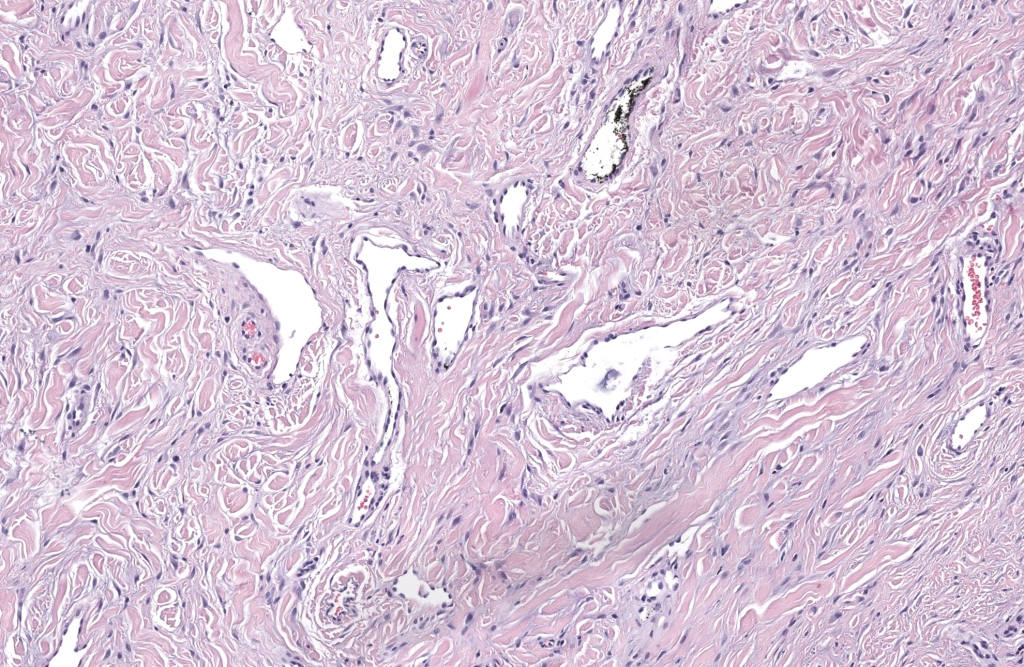

- Histología: hiperqueratosis, acantosis, colágeno grueso vertical, fibroblastos blandos, capilares finos, sin atipia significativa.Kint 1985,Wang 2024

- IHQ (si duda): Factor XIIIa+, CD34– o mínimo; VPH– si se sospecha verruga.McNiff 2005,Göktay 2015